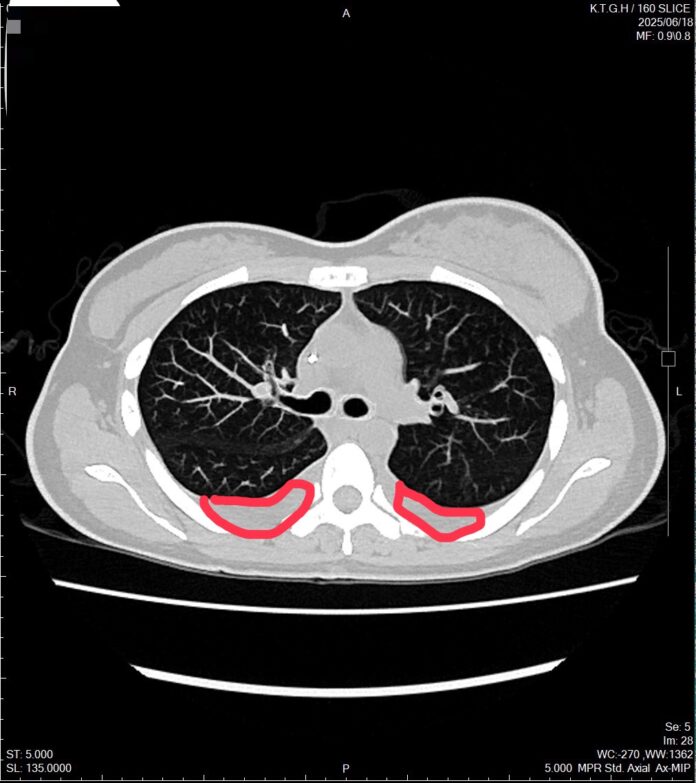

不過在2025年3月,癌症再次復發,甚至已經出現腹積水。醫療團隊進一步檢查發現,林小姐的癌細胞特徵有所變化,從原本的HER2陰性轉為HER2低表現(由0 分變為 2+,代表介於陰性與陽性之間),使其需接受新一代標靶治療。

目前林小姐已完成四次新型標靶合併荷爾蒙治療,不僅原有的呼吸困難症狀大幅改善,也能恢復正常日常活動。她分享心情說,還好有醫師幫忙,我現在過得比想像中更好。她也提醒其他患者,與其擔心病情,不如保持正向心態,積極面對治療。